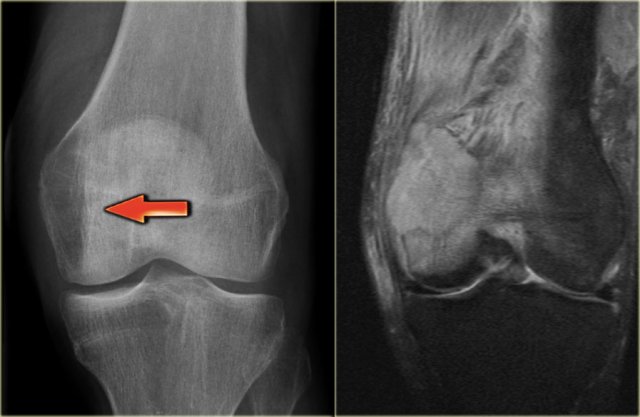

X-ray an CT-image of a typical osteoid osteoma in the proximal tibia.

Notice the sclerotic center within the osteolytic lesion (red arrow).

MR-images of the same patient demonstrate cortical thickening and extensive edema.